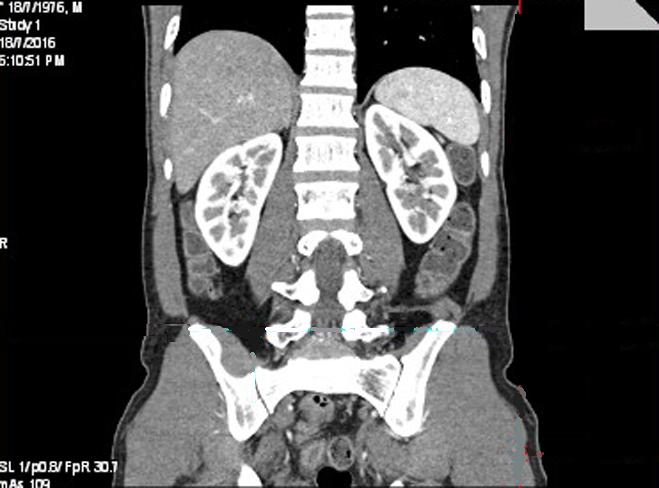

Image

radiologique TDM normal de l'abdomen avec contrast

intraveineuse , coupe axiale a travers du foie et de

la rate |

|

Même cas en coupe a travers du foie , la

vesicule biliaire et la rate |

Aspect

radiologique TDM plus C+ de la rate en coupe coronal

( frontal ) . Au phase arterielle la rate rehausse

tres hyperdense |

Aspect radiologique TDM plus C+ de la rate en

coupe sagital